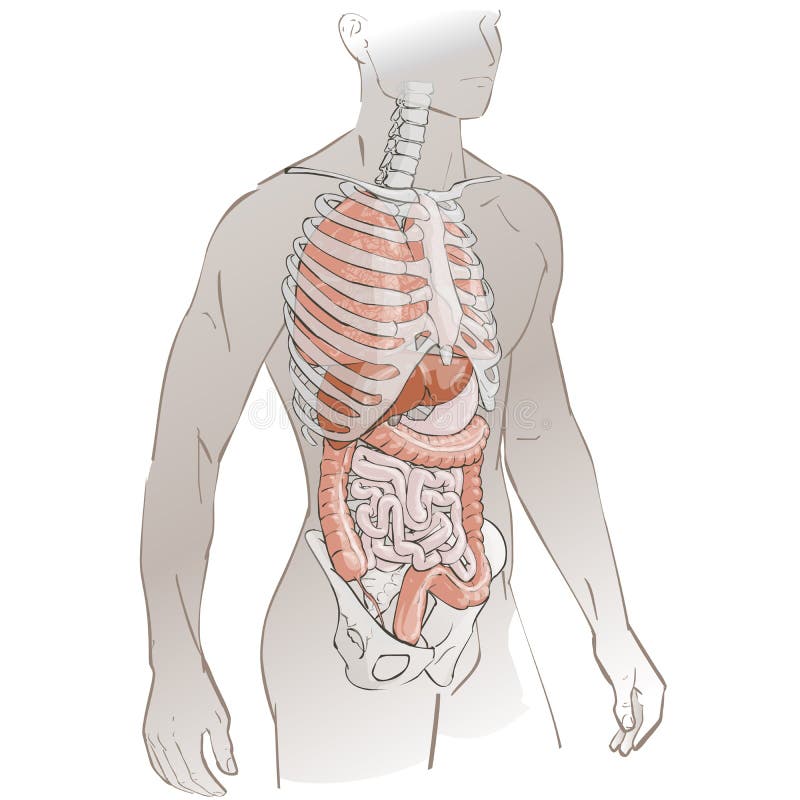

Анатомия желудка и сердца: визуализация и изучение